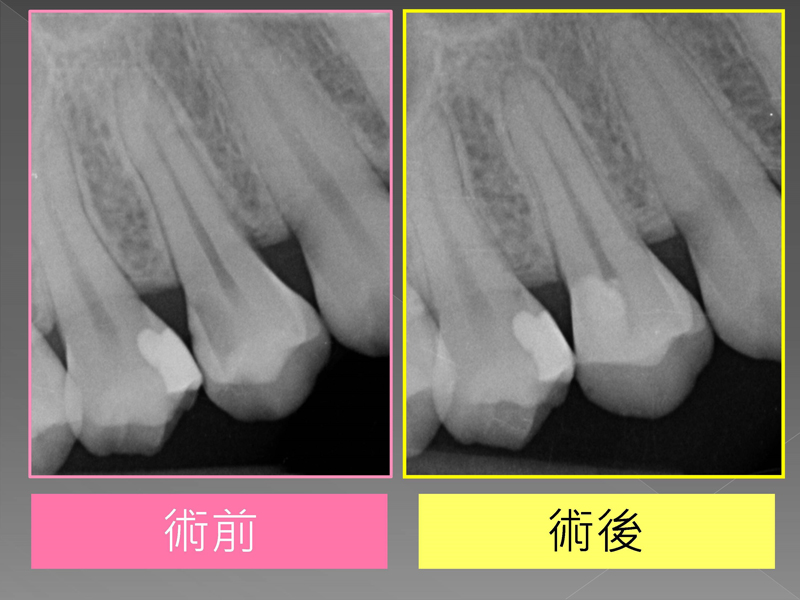

案例分享『活性牙髓治療(覆髓)- 蛀牙免根管治療的新選擇!』

[活性牙髓治療]是一項保留牙齒活性、免根管治療的新選擇喔!

- 相對健康的牙髓、單純的贋復復型方式(樹脂補牙或是嵌體),較適合- 活性牙髓治療(覆髓)的方式